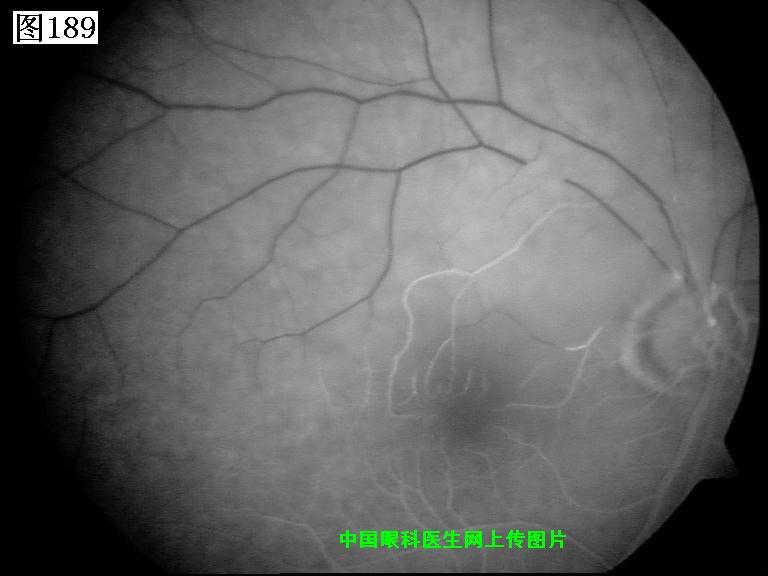

189 190 191 192